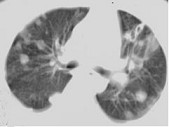

- 单项选择题女,32岁, 鼻梁双颊部出现红斑伴发热咳嗽2周,肘腕关节游走性疼痛, 请结合CT,选择最可能的诊断为 ( )

D、SLE肺部浸润